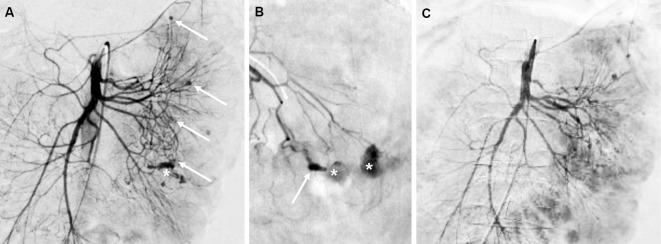

A 21-year-old woman was admitted to our hospital because of massive intestinal bleeding. She started hemodialysis due to myeloperoxidase antineutrophil cytoplasmic antibody (ANCA)-associated vasculitis (AAV) at 18 years of age. Her ANCA titers remained stable; however, her C-reactive protein increased on 5 mg/day prednisolone before admission. Computed tomography angiography revealed a ruptured jejunal arterial aneurysm. Transcatheter arterial embolization, blood transfusion and the reinforcement of steroid therapy resolved her symptoms of AAV. Our case of a young patient with AAV and medium-sized arterial vasculitis is rare and emphasizes that the ANCA titer does not always rise, especially in patients with nonrenal vasculitis flare-ups.

一位 21 岁女性因大量肠道出血而入院。她在 18 岁时因髓过氧化物酶抗中性粒细胞胞质抗体(ANCA)相关性血管炎(AAV)开始接受血液透析。她的 ANCA 滴度保持稳定;然而,在入院前,她每天服用 5 毫克泼尼松龙,C 反应蛋白升高。计算机断层血管造影显示空肠动脉破裂性动脉瘤。经导管动脉栓塞、输血和强化激素治疗缓解了她的 AAV 症状。我们的这个年轻 AAV 合并中等大小动脉血管炎的病例比较少见,强调了 ANCA 滴度并不总是升高,尤其是在非肾血管炎发作的患者中。